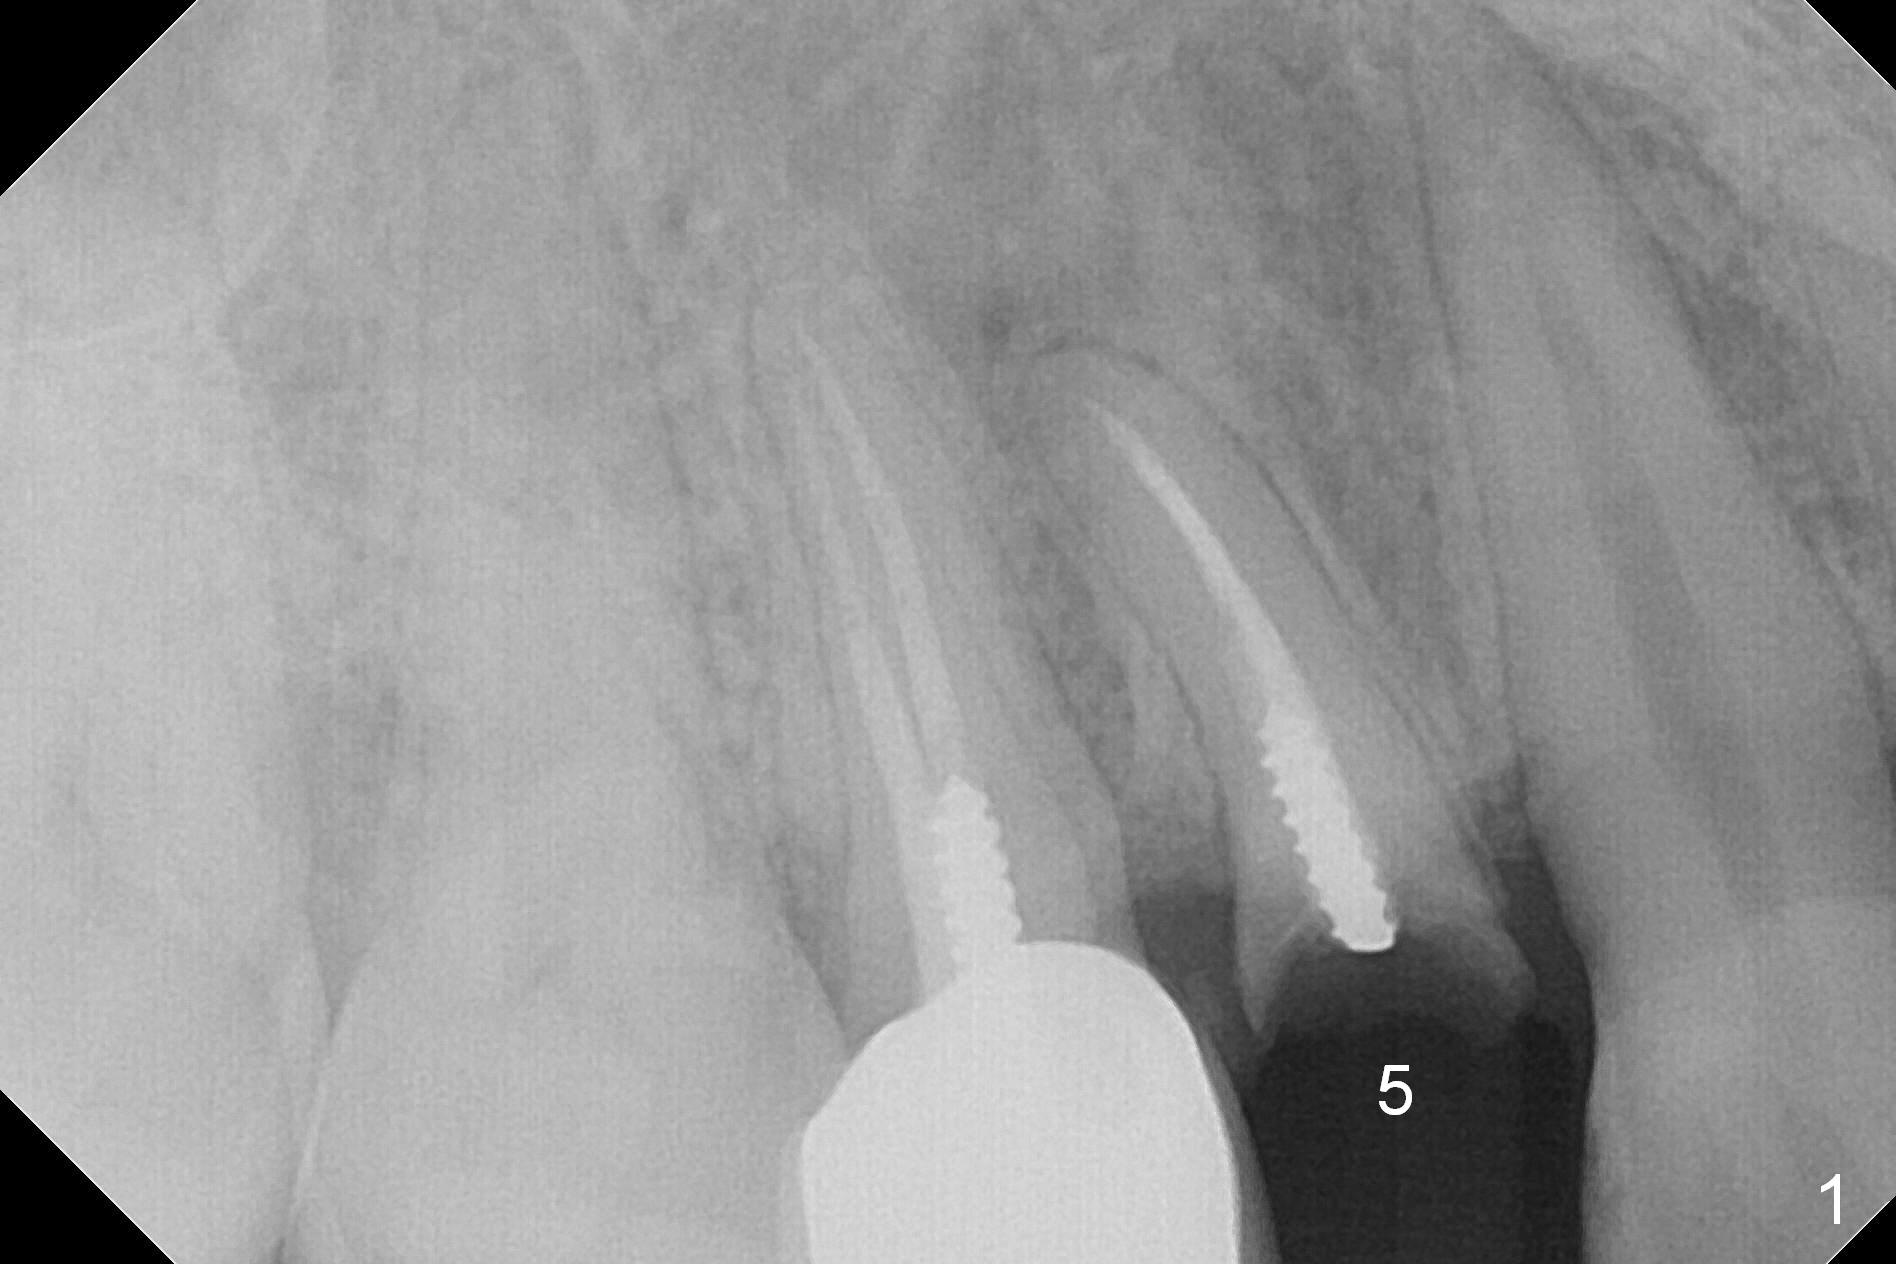

A 34-year-old man (smoker, half a pack a day) has residual root at #5 (Fig.1) with large periapical radiolucency (Fig.2 red dashed line).  Since the root curves distally (Fig.3 black area, Clindamycin), osteotomy will be established in the mesial wall (red long arrow).  A 3.8x16 or 18 mm implant is to be placed for primary stability (Fig.4).  To reduce periimplantitis associated with smoking, place the implant deep.  The implant appears to have better surface treatment.  Pack sufficient bone graft and membrane.  Immediate provisional should have good seal.  To place the implant deep, osteotomy will be attempted with a long 1.5 mm pilot drill (PA), followed by 2 mm one with extension and 3.0x18 mm drill.